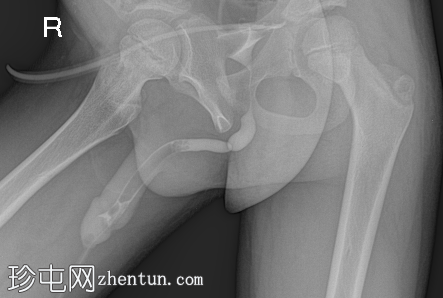

盆腔位

逆行尿道造影显示远端球部尿道存在持续性短段(<1 cm)、环周性明显狭窄,近端轻度扩张。造影剂可自由进入后尿道和膀胱,无外渗。

阴茎尿道充盈缺损为医源性,由注入的气泡引起。